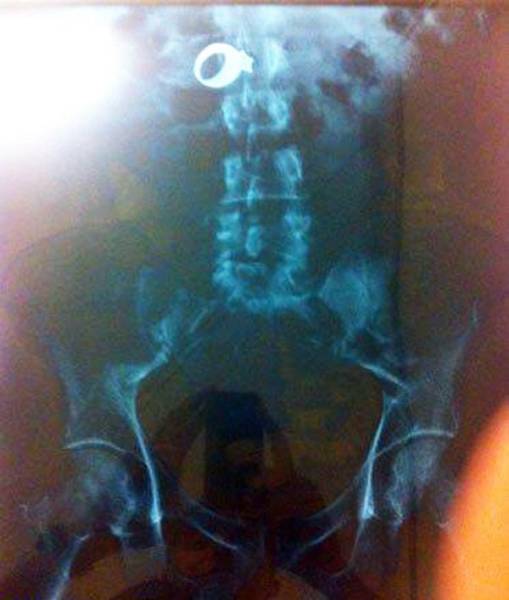

#20 Hääsormus